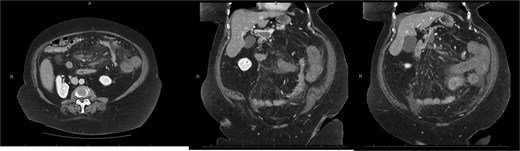

A 76-year-old female with a 3-day history of left upper abdominal pain, vomiting, and haematochezia. Her history included pulmonary embolism, multiple deep vein thromboses, with no ongoing anticoagulation, and an open partial colectomy for complicated diverticulitis a decade earlier. On admission, she was afebrile but tachycardic and showed localized tenderness in the left hypochondrium. Laboratory revealed leucocytosis with a white blood cell count (WBC) of 12 G/L, elevated C-reactive protein (CRP) of 46 mg/L, and hyperlactatemia of 2.6 mmol/l. Enhanced computed tomography (E-CT) revealed jejunal venous ischemia in the left upper quadrant, secondary to extensive porto-mesenteric thrombosis with reduced bowel wall enhancement, distention, and free intraperitoneal fluid (Fig. 1). She was managed conservatively with unfractionated heparin (UFH) with a bolus of 5000 U/l followed by 30 000 U/l/24 h (target INR 0.35–0.7), Piperacillin-Tazobactam, and bowel rest. After 48 h of monitoring in the intensive care unit (ICU), she exhibited marked biological and clinical improvement. E-CT on the third day showed restored bowel wall enhancement and stable porto-mesenteric thrombosis (Fig. 2). She was discharged on therapeutic low molecular weight heparin (LMWH) with enoxaparin sodium 120 mg every 12 h. At the 3-month follow-up, E-CT revealed near-complete thrombus resolution, without intestinal sequelae (Fig. 3).

Follow-up E-CT 72 h after conservative management in the first patient. Dashed arrows show improved viability of the small bowel with bowel wall enhancement. White arrows revealed the stability of the extended porto-mesenteric thrombosis.